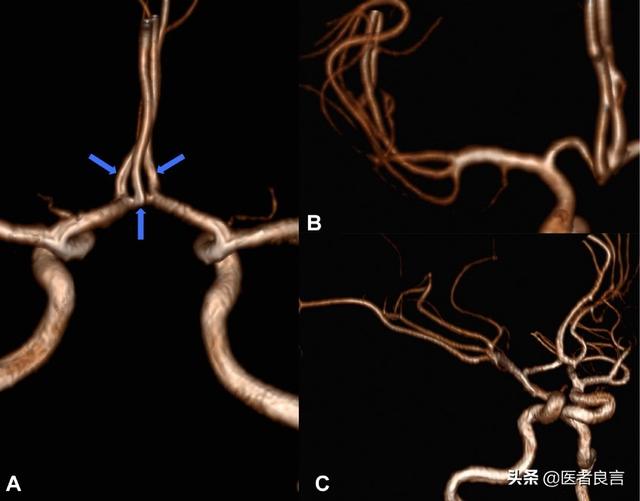

冠状動脈性心臓病は、冠状動脈のアテローム性動脈硬化性狭窄に基づく一連の心血管系疾患の総称であり、通常、冠状動脈の狭窄の程度が50%以上で診断され、心臓の血液供給と酸素供給に影響を及ぼし、疾患発作の重症度に応じて、無症状で無症候性の心筋虚血、狭心症、急性梗塞、虚血性心疾患、心不全、突然死に至る冠状動脈狭窄など、さまざまな病態がある。これらの問題はすべて冠動脈疾患の傘下にある。

冠状動脈疾患の発生は、このような病理学的基礎に基づいており、心臓に血液を供給する冠状動脈は、徐々に脂質を蓄積し、プラークを形成し、徐々に硬化し、狭くなり、最終的に狭窄の程度が心臓への血液供給に決定的な影響を形成した後、冠状動脈疾患の問題が形成される。したがって、冠状動脈性心臓病の発生に対して、もし積極的に発症の危険因子を制御するために介入することができなければ、冠状動脈の狭窄の初期段階では、非常に多くの場合、それは隠されている可能性があり、診断せずに検出することができず、このような状況であれば、プラークの破裂が発生すると、冠状動脈の梗塞(急性梗塞)、または心筋の局所的な虚血のために電気生理学的な障害と深刻な心拍数の出現に起因する不整脈や心停止が発生し、いずれも死に至る危険性がある。

冠動脈疾患の問題で、より深刻な冠動脈狭窄、頻発する不安定狭心症、急性心筋梗塞と診断された方にとっては、心臓への血液供給が深刻な影響を受け、冠動脈疾患のリスクが保存的な生活習慣の改善や薬物療法では効果的にコントロールできなくなったことを意味します。 この場合、医師にリスクを評価してもらう必要があり、一般的には、心臓への血液供給を開放して改善し、心筋の損傷や心機能の障害のリスクを軽減するために、ステント留置術やバイパス移植術(バイパス・グラフト術)を行う必要があります。この場合、リスクは医師によって評価されるべきであり、通常、心臓への血液供給を開放して改善し、心筋への損傷や心機能障害のリスクを軽減するために、インターベンショナル・ステント留置術やバイパス・グラフト術(バイパス・グラフト術)が必要となります。